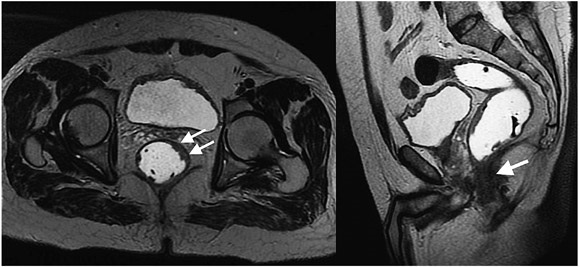

La estadificación del tumor depende directamente de su relación con la capa muscular propia y de la invasión con los órganos adyacentes (8). Un tumor T1 es aquel que se encuentra confinado a la mucosa, un tumor T2 es el que se extiende hasta la muscular propia (figura 3), un tumor T3 invade y se extiende más allá de la muscular propia (T3 temprano menor de 5 mm o T3 avanzado mayor de 5 mm) (figuras 4 y 5) y un tumor T4 es aquel que invade los órganos pélvicos (figura 6) (15). Los vasos pélvicos, la fascia parietal pélvica y la fascia mesorrectal no son considerados órganos (8).

Hacer la diferencia entre lesiones estadio T2 y T3 no siempre es sencillo, ya que las reacciones desmoplásicas o los cambios de fibrosis generan especulación de la grasa perirrectal y no siempre es posible diferenciar cuando hay o no presencia de componente tumoral en estas lesiones, lo que lleva a una sobrestimación de la estadificación (14,18,23,30-32). Esta situación es particularmente importante en pacientes que hayan sido tratados con radioterapia; en este escenario la presencia de lesiones nodulares, a diferencia de la espiculación, favorece el diagnóstico de residuo o recidiva tumoral sobre los cambios por radioterapia.